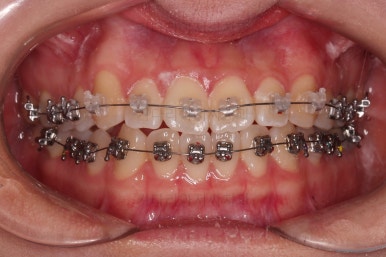

1. 처음 내원 시의 입안의 모습

부산치아교정잘하는곳 키다리아저씨치과에 처음 내원하셨을 당시의 입안 모습입니다.

얼핏 보면 많이 삐뚤어지지는 않은 편인데, 눈에 바로 띄는 앞니가 뻗쳐 있으면서 획 돌아있는데요. 정렬이 필요한 상황이었습니다.

어금니쪽은 많이 삐뚠 편은 아니었으며, 윗니 앞니가 많이 앞으로 뻗쳐 있는 상태였습니다.